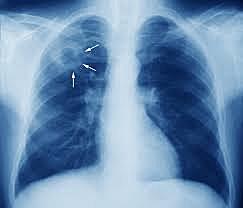

As soon as John heard WWI was declared he took off to Prince Albert to to enlist but got rejected because of how weak his lungs were. (Later found out he had TB) A few weeks later John saw RCMP looking for members so he applied and made it past the examination.

As the war went on Jack had issues with himself and had to fight his own battle. For months he was feeling unwell and finally decided to consider a doctor cause he thought something may actually be wrong. The doctor diagnosed him with TB